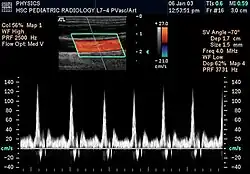

W obrazowych badaniach diagnostycznych cenną informacją jest nie tylko kształt anatomicznych struktur, lecz także kierunek i prędkość poruszania się tkanek. Ruch takich płynów ustrojowych jak krew można obserwować, mierząc zmiany częstotliwości oraz fazy fal dźwiękowych odbitych od płynącej cieczy[25].

Udoskonaleniem konwencjonalnych aparatów ultrasonograficznych było wprowadzenie ultrasonografii dopplerowskiej. Jeżeli głowica ultradźwiękowa potrafi rejestrować nie tylko opóźnienie echa wysyłanego dźwięku, lecz również jego częstotliwość, wtedy na obrazie diagnostycznym można umownymi kolorami zobrazować ruch organu lub płynu ustrojowego[26].

W badaniach dopplerowskich USG stosuje się technikę wiązki ciągłej w której aparat generuje ciągle wiązkę fal, oraz impulsową, w której aparat generuje impulsy odpowiadające połówce okresu fali, po której następuje przerwa w czasie której odbierana jest analizowana fala[26].

Przykładem może być echokardiografia. Dla kardiochirurgów bardzo ważne jest określenie nie tylko struktury anatomicznej serca, ale również prędkości i kierunku ruchu krwi przepływającej w tej biologicznej pompie[27]. Obserwacja bijącego serca płodu umożliwia wykrycie wad rozwojowych jeszcze w łonie matki.